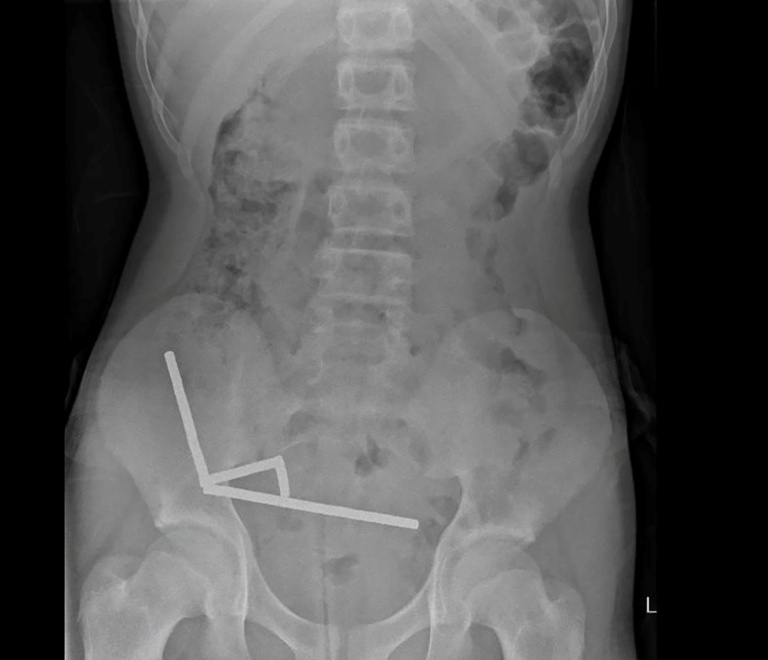

An X-ray showed the magnets had clumped together in four straight lines inside the child's intestines.

"These appeared to be in separate parts of bowel adhered together due to magnetic forces," they said.